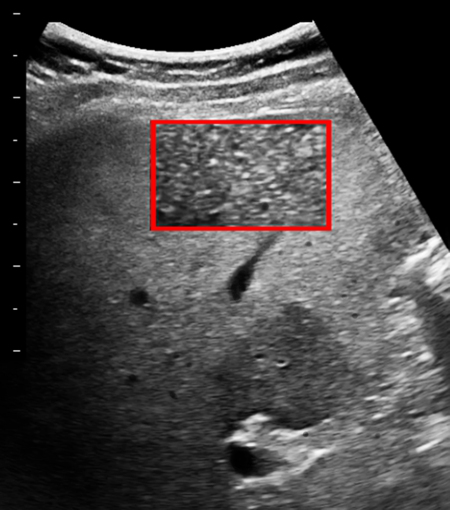

Qualitative assessment of liver fat with conventional ultrasound. (A …

Practice of Ultrasound: Part 13 — Liver fat and fibrosis